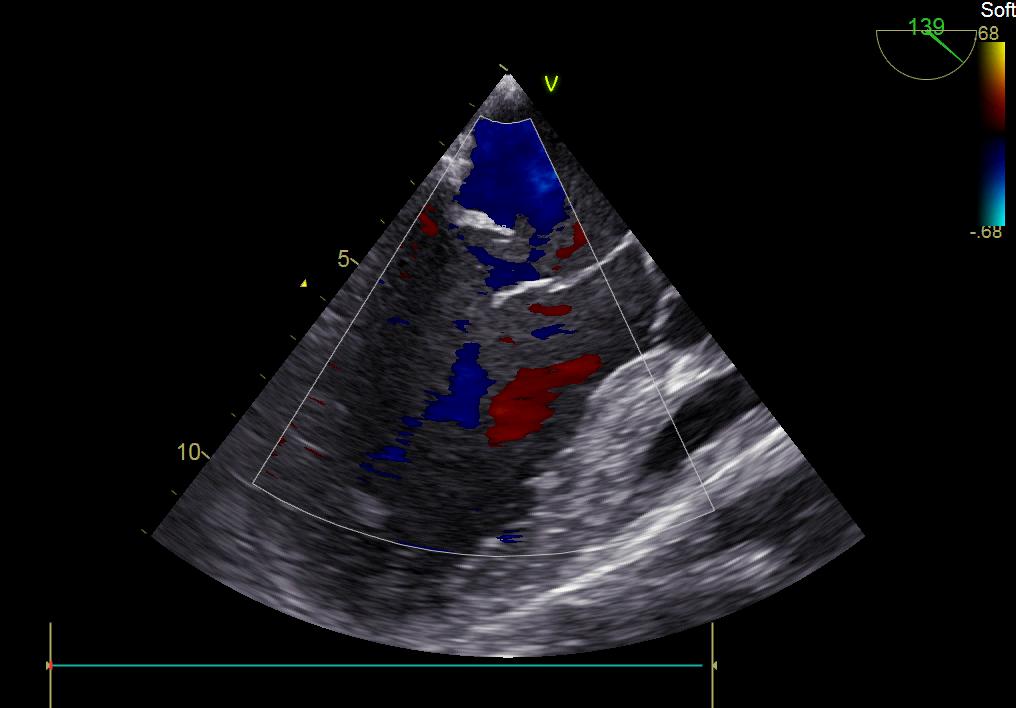

患者何某,42歲男性,因心功能不全入住我院心胸外科,心臟彩超提示二尖瓣后葉脫垂伴有重度返流及心臟擴大,在迅速糾正心衰后,手術(shù)便提上日程,心胸外科廖金文主任多次組織全科及兄弟科室討論,在二尖瓣置換及成形術(shù)上,最終決定采取二尖瓣成形術(shù)。為保證手術(shù)安全,討論圍手術(shù)期各個細節(jié),所謂細節(jié)決定成敗,因為術(shù)前的細致全面,加上術(shù)中的一絲不茍及術(shù)后的精細化管理,患者術(shù)后恢復(fù)順利,健康出院,復(fù)查心臟彩超未見二尖瓣返流。

術(shù)前彩超

術(shù)后彩超